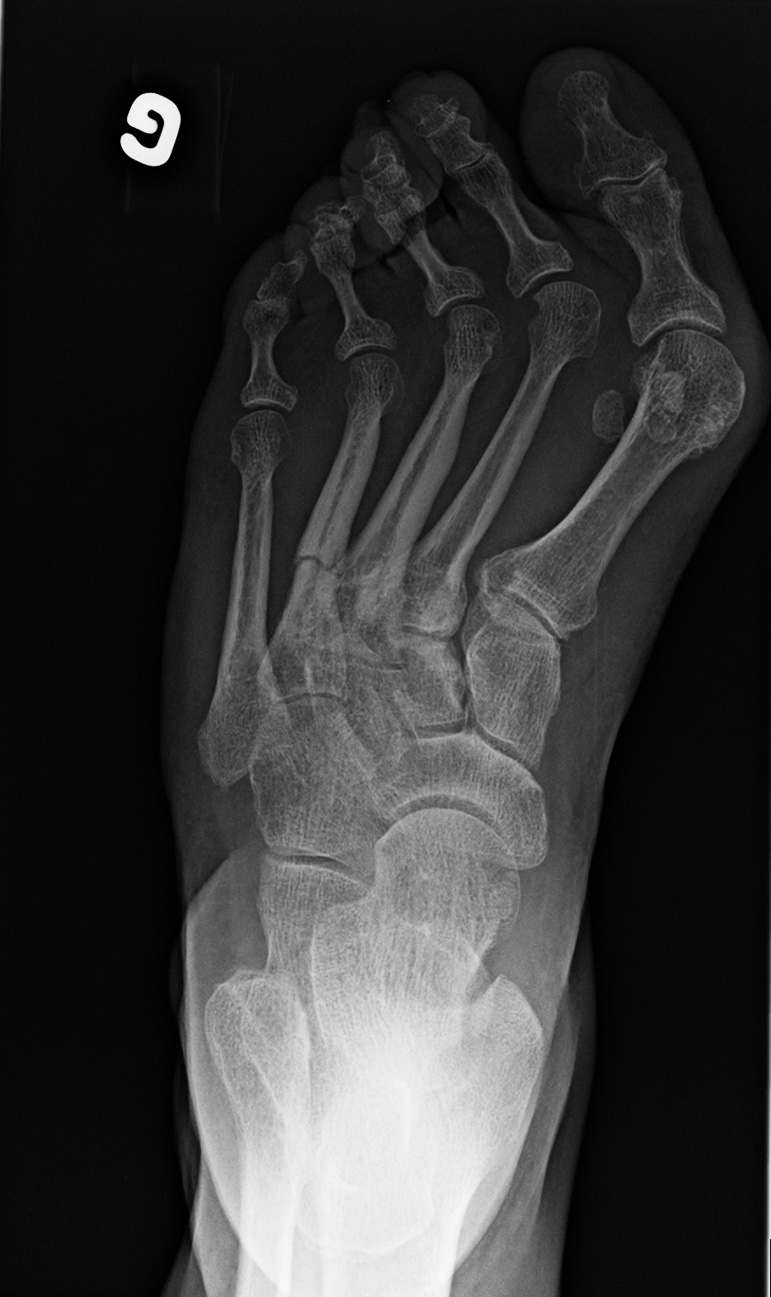

Oblique

• Anteroposterior

• Lateral

• Oblique

• Standing view of the feet